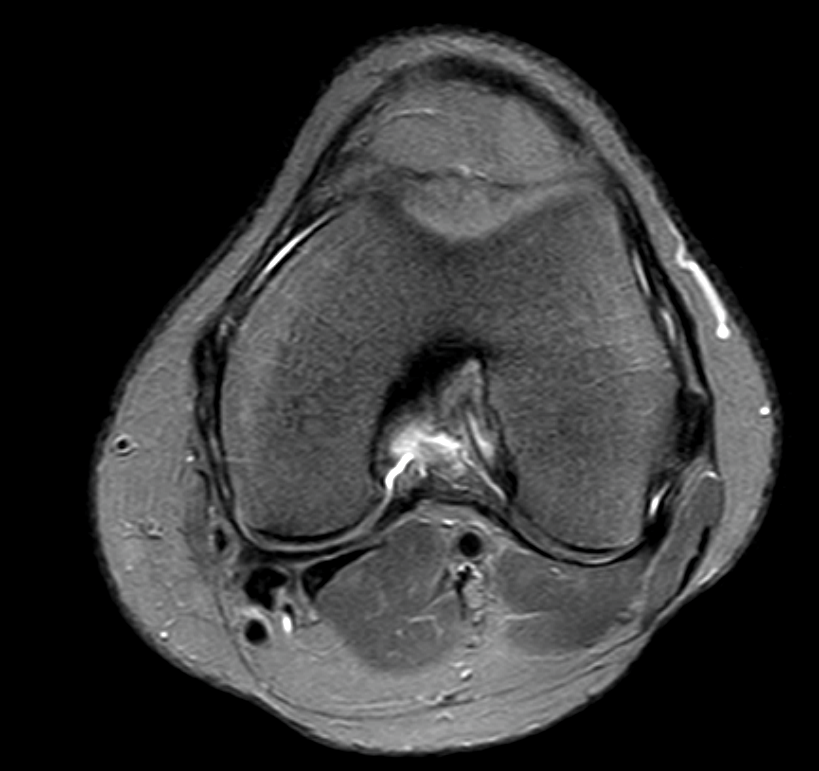

Kann mir jemand bei der Auswertung von MRT Bildern am Knie geben? (Arzt, Bluterguss, Radiologie)

MRT Befund rechtes Knie ist da irgendwie ne OP notwendig?

Meniskus gerissen MRT? (Knie, MRT Befund, Radiologie)

MRT Knie, weiße Schatten + Meniskusriss? (Schmerzen, Befund, Kniegelenk)